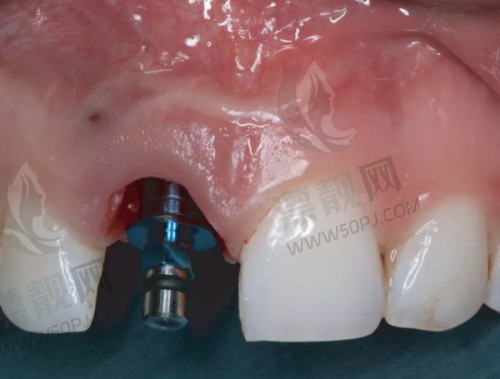

- 肖步挺院长 — 原南加州大学种植大师,擅长数字化即刻种植 + All-on-4/6,全口重建级别干将。

- 数字导板种植+微创植入:更快捷修复快,术后少肿

“设备比我去的大医院还新,种牙当天就能吃,对那种怕疼的朋友太友好了!”